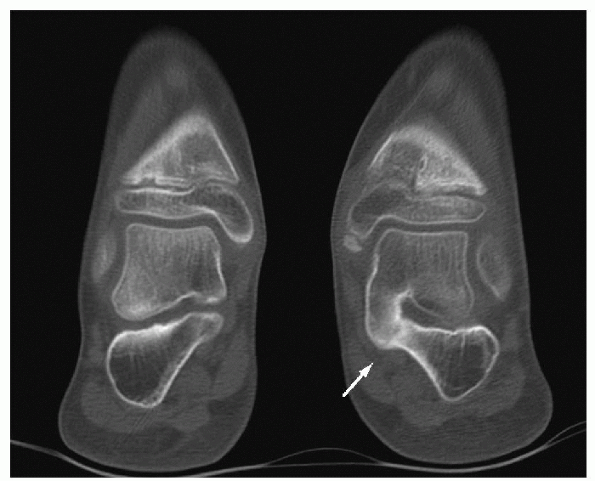

-

If there is middle facet TCC (Fig. 4.4-4)

![]() |

Figure 4.4-4

Coronal computed tomography through both hindfeet showing a middle facet talocalcaneal osseous coalition compared with a normal middle facet on the contralateral foot. |